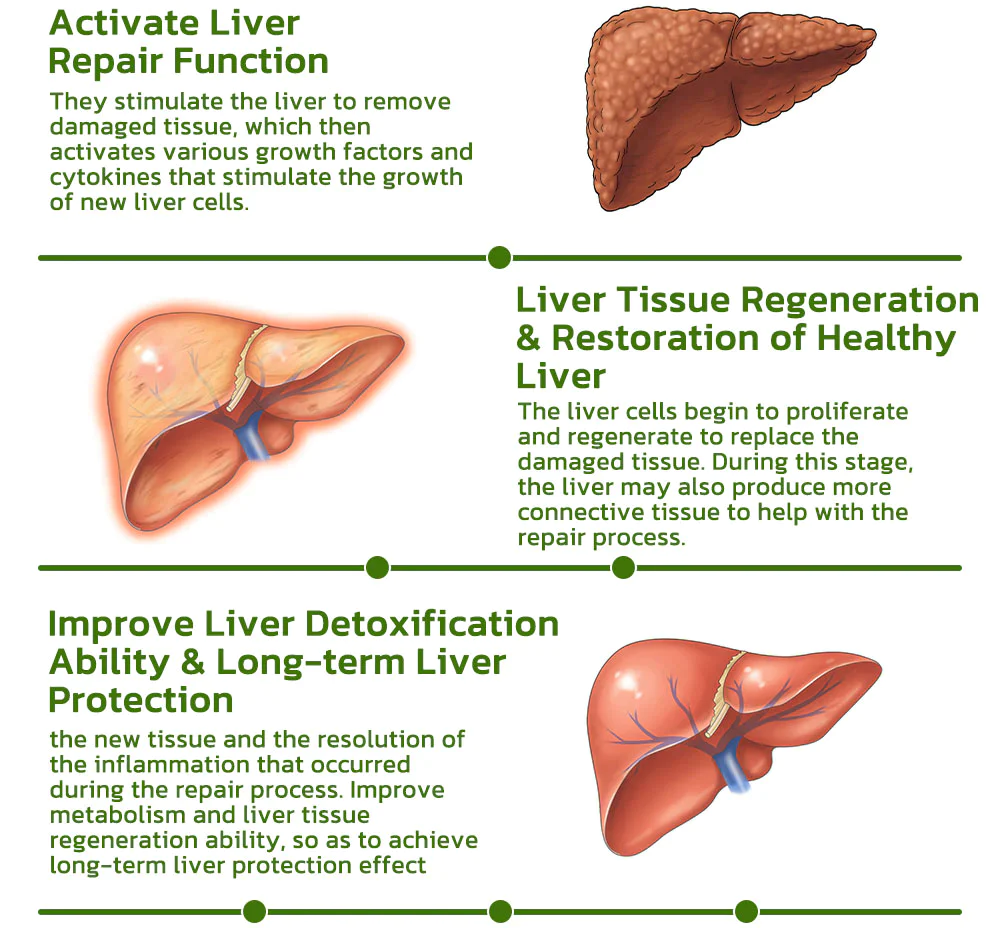

Dr. Shinichiro Hanada’s research team has created the BLUESKY Liver Care Patches, cleverly formulated with a pure herbal blend of vegan ingredients. Within 8 weeks, these patches work to repair the liver and restore its normal function, enhancing the body’s detoxification abilities. Additionally, they may help reduce excessive liver fat and promote the regeneration of new liver cells.

These substances are absorbed into the bloodstream through the capillaries of the skin and then act on the liver, enhancing detoxification and liver tissue regeneration. Compared to conventional liver cleansing treatments, this method is 25% more effective in liver detoxification and regeneration than pharmaceutical treatments.